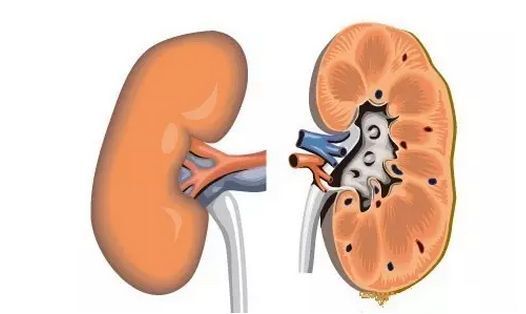

肾是泌尿系形成结石的主要部位,其他任何部位的结石都可以原发于肾脏,输尿管结石几乎均来自肾脏,而且肾结石比其他任何部位结石更易直接损伤肾脏,因此早期诊断和治疗非常重要。那么,肾结石能否遗传呢?

1、局部损伤:肾结石的体积如果较小且活动较大,局部组织的受损就只有轻微的程度,肾结石如果体积较大并且呈鹿角状,就会产生纤维组织增生、中性粒细胞、溃疡以及淋巴细胞浸润,导致肾脏纤维化和肾盂和肾盏上皮细胞脱落。

2、肾脏受损:如果肾结石出现长期肾盂积水、排尿困难、梗阻上部压力过大、肾脏血流减少、会导致肾萎缩小、肾功能减小、肾小管坏死、甚至失去肾功能。